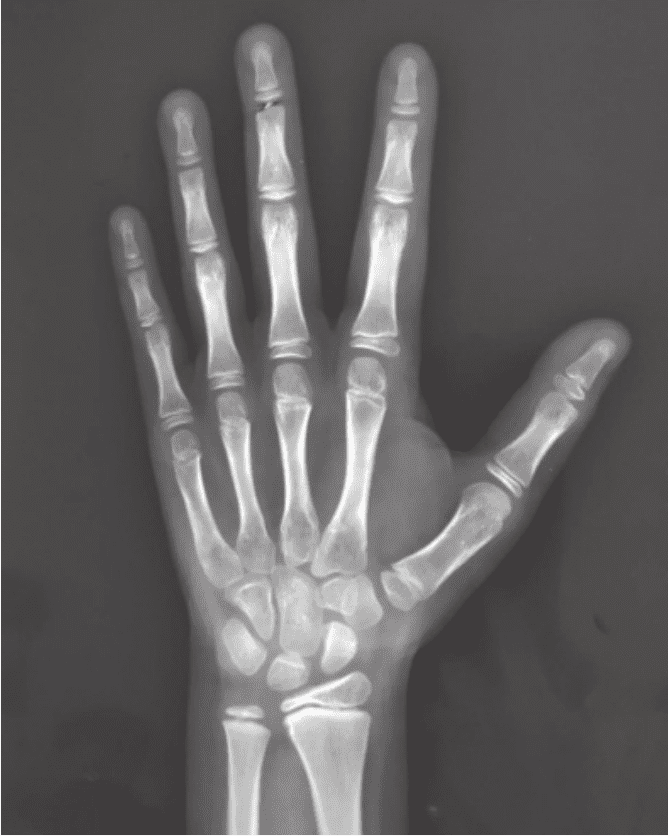

看孩子骨生理年齡一般要拍X片來進(jìn)行判斷。如果孩子是右利手,那么在拍片子的時(shí)候要拍左手;如果孩子是左撇子,那就要拍右手,這樣得到的結(jié)果會(huì)更可靠。如果年齡到了一定程度,還要拍其他的部分,比如腳后跟、肘關(guān)節(jié)、骨盆等。

在北京協(xié)和醫(yī)院,一般比較推崇的是圖譜法。根據(jù)圖譜,我們倒推骨生理年齡的情況,再結(jié)合生長發(fā)育的整體情況,測算他的骨骼到底處于生長發(fā)育的什么階段。這對于我們來說是一個(gè)非常重要的手段。當(dāng)然,這個(gè)計(jì)算過程比較煩瑣,我們一般會(huì)借助專門的計(jì)算機(jī)系統(tǒng)來進(jìn)行輔助分析。父母可能沒辦法計(jì)算清楚,但可以請大夫根據(jù)骨生理年齡片子幫忙計(jì)算。